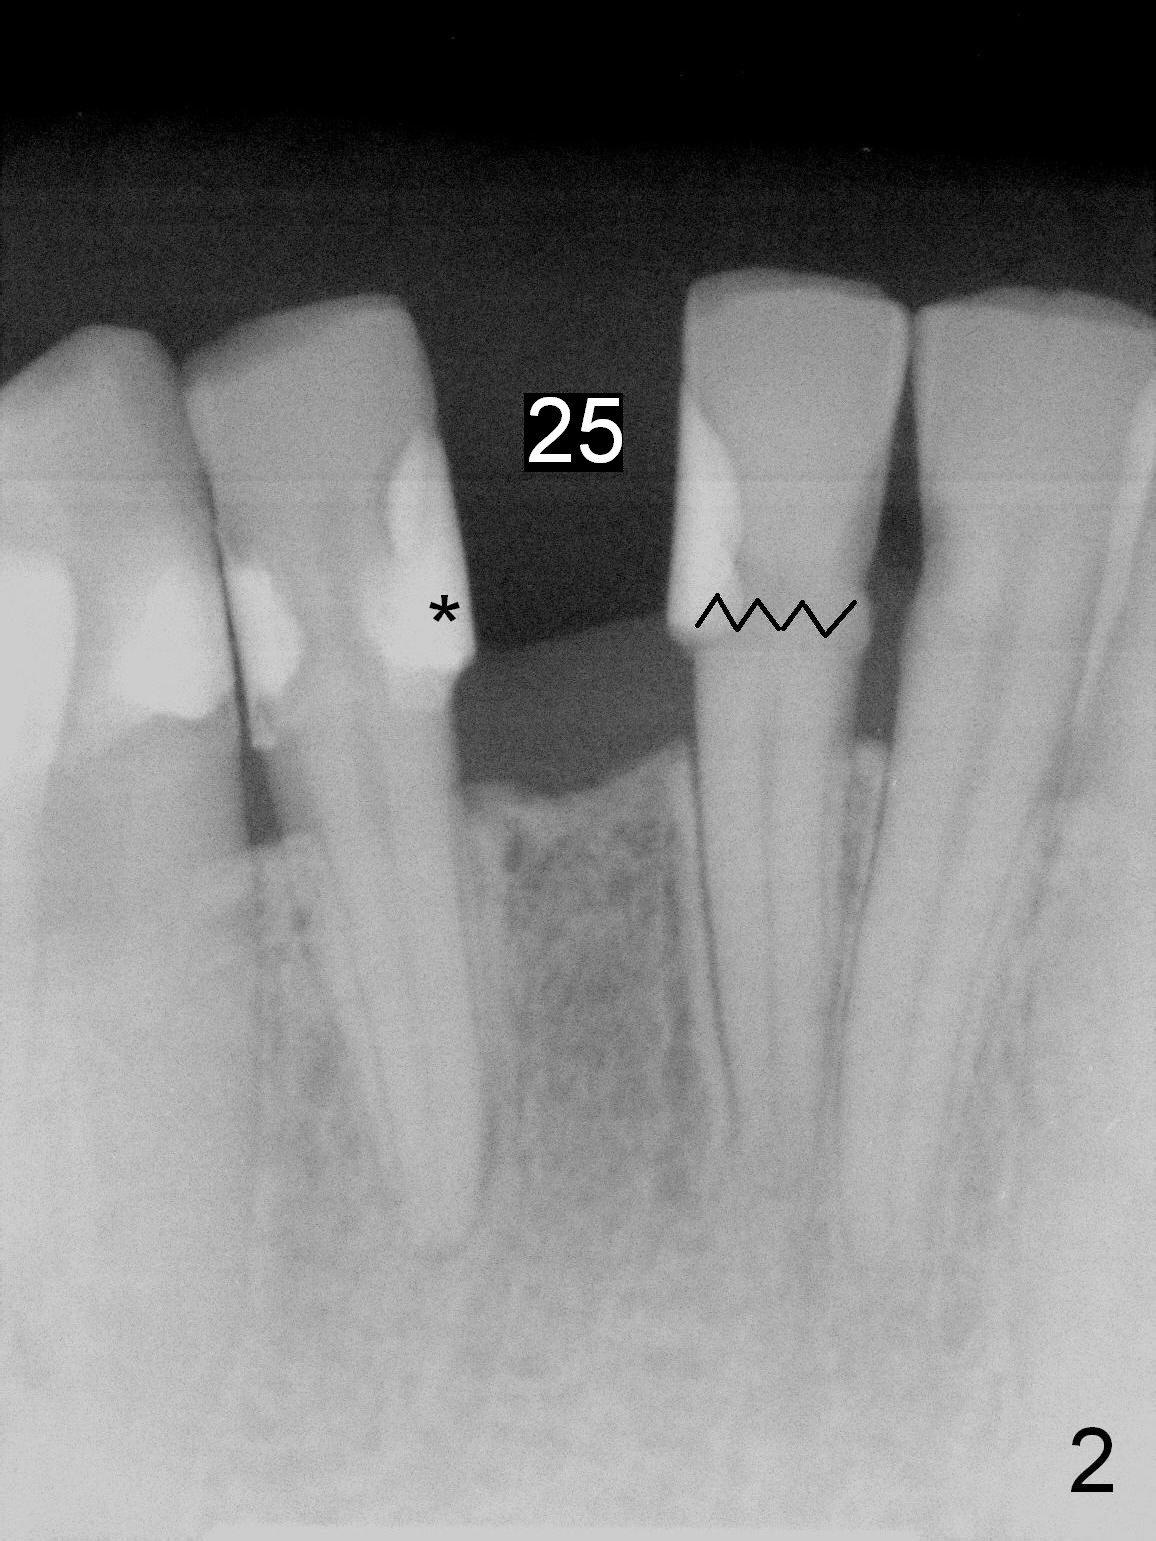

A 53-year-old woman (WX) had several missing teeth with a lower flipper (Fig.1,2, conditions 2 years ago). Recently the tooth #24 fractured equigingival (Fig.2 saw-toothed line). The edentulous area at #25 is narrow buccolingually (Fig.4a). Start osteotomy lingually (L, Fig.4b red circle). As the osteotomy increases (Fig.4c red circle) and a 2 or 2.5 mm 1-piece DIO implant is placed (Fig.4d green circle), the weaker buccal (B) plate is being expanded buccally.

A 3 or 3.5 mm 1-piece implant is placed at #24 (Fig.3) after Metronidazole socket soaking. The larger one is chosen (3.5 mm (Tatum)) if the implant at #25 fails to be placed. A dummy implant is placed partially to test trajectory. If the latter is bad, use an angled 1-piece one (Tatum). The composite overhang (Fig.2 *) is to be trimmed (Fig.3 red line). Take preop photos to show the concave buccal plate (Fig.4a) and intra- and post-op ones to show bone expansion (Fig.4b-d).